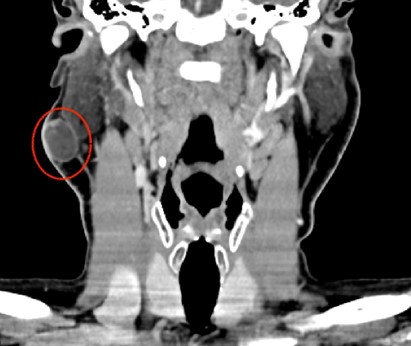

The CT scan of the neck with intravenous iodinated contrast revealed an oval image measuring 21 x 16 x 24 mm (AP x T x CC) located in the subcutaneous tissue at the level of the mandibular angle and the tail of the right parotid gland, superficial to the deep cervical fascia. It presented hypodense contents (probably cystic), with a thin, hyperenhancing wall and a small, 7 x 5 mm intraluminal hyperdense image adjacent to its posterolateral wall. The findings were suggestive of a soft tissue tumor, but radiologically nonspecific. No pathologically apparent laterocervical lymphadenopathy was observed.

Imagen 1: coronal CT scan shows a nodule on the right side, superficial to the deep cervical fascia.